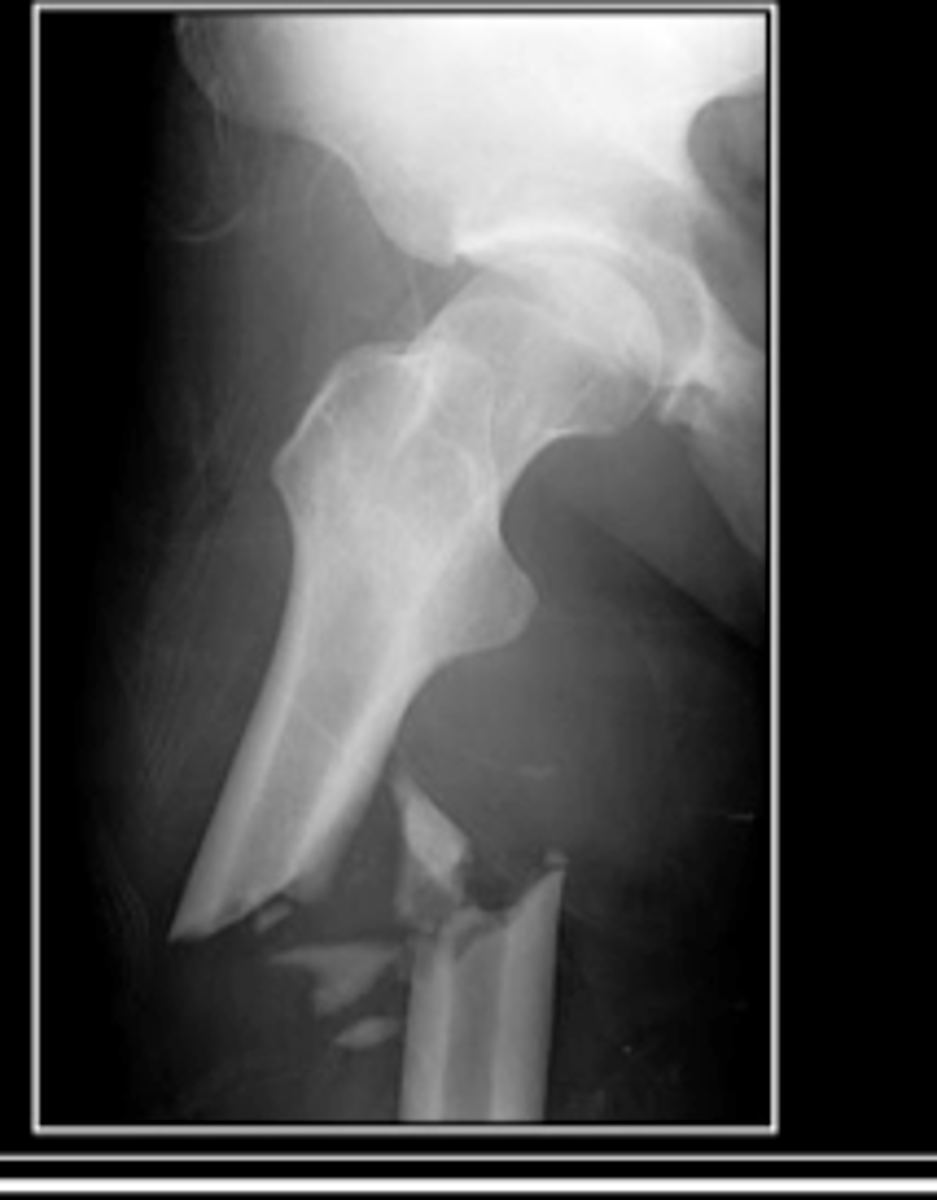

impacted

fracture (usually seen in long bones) where broken bone ends are forced into each other

ball and socket

synovial joint containing a bone with a spherical head that fits into a round socket in another bone; i.e. shoulder & hip